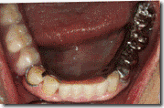

患者A先生

上顎 正面 下顎

患者B小姐

以上兩位患者口內狀況非常複雜,要制定一個好的治療計畫,

不只要考慮到患者的牙齒條件,

還要顧及患者意願、時間、金錢、評估可獲得的結果等等。

所以像這類型的Case 醫師通常在初步的溝通後會先做出一兩個不同的治療計畫,

再和患者解釋,了解患者接受程度。